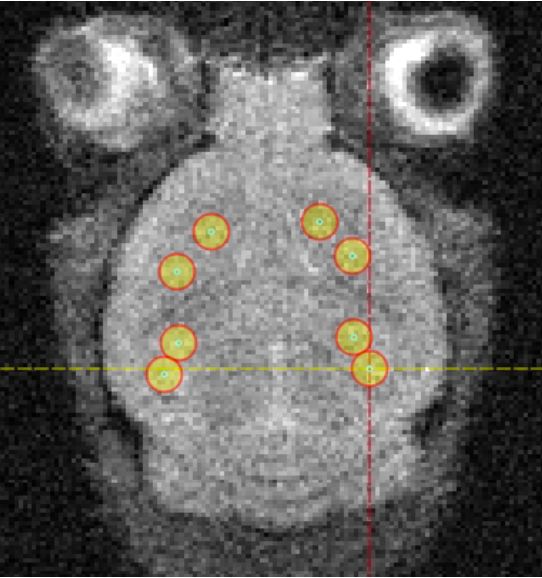

The project is currently conducted in preclinical mouse models of glioblastoma, which provide a controlled environment for evaluating therapeutic delivery, imaging accuracy, and treatment response before translation toward clinical applications.

Radiolabeled PSMA ligands are used for theranostic purposes. Copper-64-labeled PSMA enables high-resolution PET imaging and quantitative assessment of tumor uptake, while copper-67-labeled PSMA is applied for SPECT-guided radiotherapy. Together, these radionuclides allow the same molecular construct to be used for diagnosis, treatment planning, and therapy.

Focused ultrasound plays a key role in the NORTHCARE strategy through the use of Acoustic Cluster Therapy (ACT). ACT involves the activation of microbubbles within tumor blood vessels using focused ultrasound, leading to a temporary and localized increase in vascular permeability. This effect enhances the delivery of PSMA-targeted radiotherapeutics to the tumor tissue.